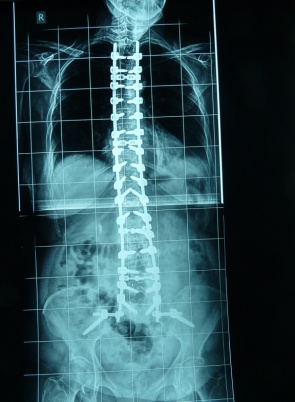

Εικ. 3: α. Προεγχειρητική και β. Μετεγχειρητική φωτογραφία της στάσης του σώματος πριν και μετά τη διορθωτική χειρουργική επέμβαση.

Καθοριστικό σημείο για την επιτυχή χειρουργική αντιμετώπιση της σκολιωτικής παραμόρφω-σης του ενήλικος είναι η αποκατάσταση της οβελιαίας ισορροπίας του σώματος.